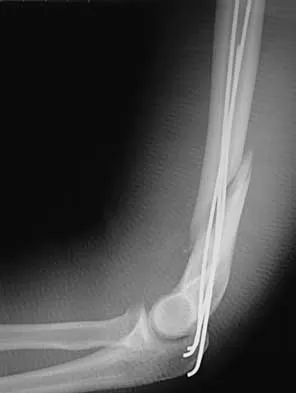

Question 32High Yield

A 54-year-old woman sustained an elbow injury 3 months ago that was treated with open reduction and internal fixation. She now reports pain and limited elbow motion. Radiographs are shown in Figures 10a and 10b. Treatment should now consist of

Explanation